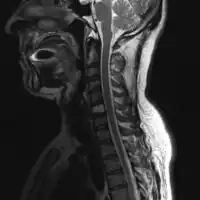

1.a. X-ray: solitary plasmacytoma upper arm near shoulder -

| Solitary plasmacytoma in the long bone of the upper arm | |